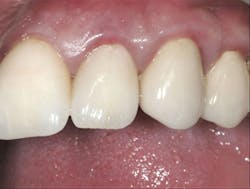

3. All supragingival coronal tooth structure gone. Endodontic treatment usually necessary. Post and core placed. Enough remaining tooth structure to allow at least 2 mm of ferrule around the margin portion of the tooth preparation, or bony crown lengthening accomplished allowing the ferrule. Nonabusive occlusion (Figures 1 and 2)-This clinical situation requires in-depth informed consent from the patient, since saving the tooth is expensive and the long-term success of the clinical result is questionable. If the treatment fails, an extraction, along with an implant and crown or a fixed prosthesis, will be required, further adding to the patient cost. The potential for success is markedly reduced in this situation. However, proper placement of a post and core and crown allows clinical success in a significant percentage of cases. If the patient feels more comfortable with an implant after proper informed consent, that treatment should be strongly considered. However, in my experience, many patients prefer to retain the affected tooth, in spite of the reduced potential for long-term service. That is also my personal preference.